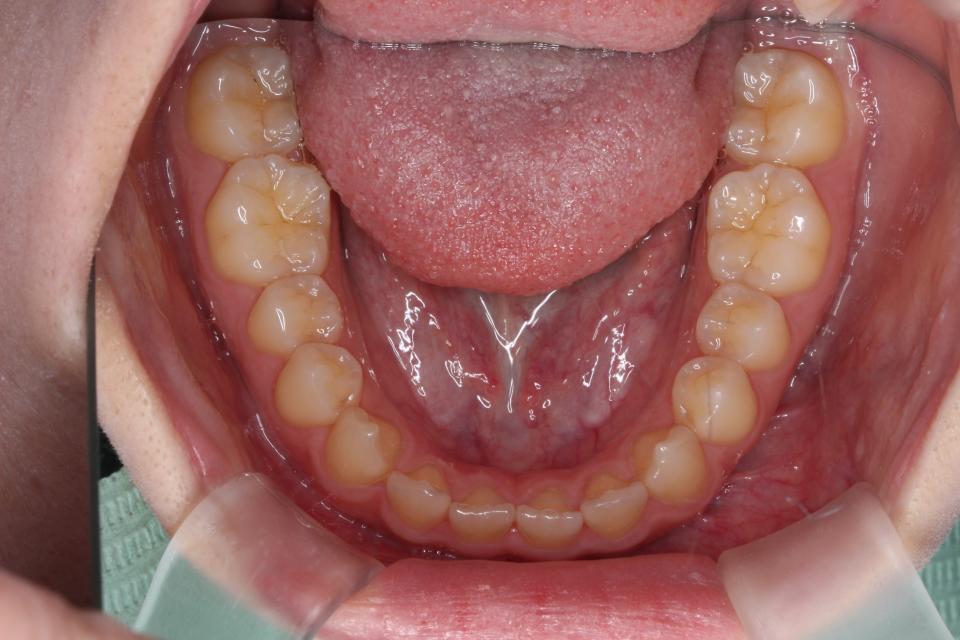

矯正治療前

20代女性の患者さんです。

上下の歯にワイヤー(マルチブラケット装置)をつけて治療しました。

きれいに並びきるために歯のやすりがけ(IPR)も行っています。